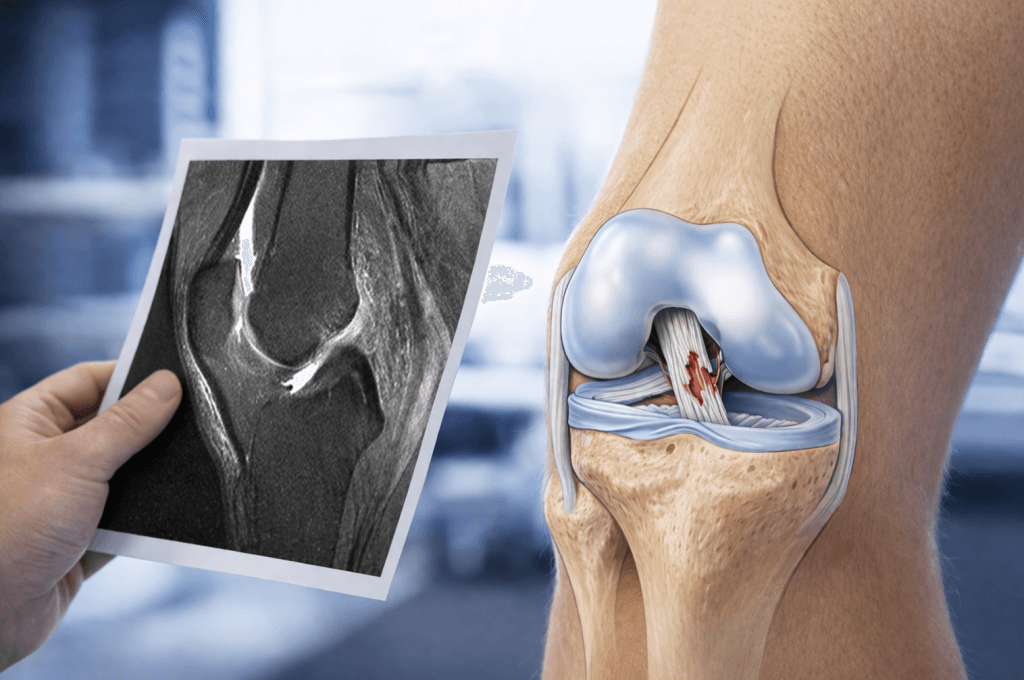

A partial ACL tear occurs when some fibres of the anterior cruciate ligament (ACL) remain intact after injury. It is a common diagnosis on MRI scans, particularly in patients who have injured their knee playing football, soccer, or netball. However, one of the most important things patients should understand is that not all partial ACL tears are the same. And more importantly, not everything labelled a ‘partial tear’ on MRI behaves like a true partial ACL tear.

Can an MRI accurately diagnose a partial ACL tear?

MRI is an important tool in diagnosing ACL injuries, but it has limitations. An MRI may show that some ACL fibres are still intact, leading to the diagnosis of a “partial tear.” However, MRI cannot reliably determine whether the ACL is functioning properly.

A ligament that appears partially intact on MRI may still behave like a non-functional ACL if it does not provide stability. This is where many patients are misdiagnosed.